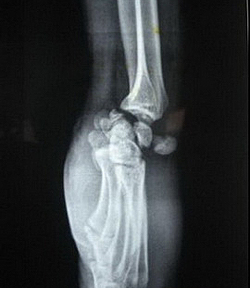

Для установления диагноза важную роль играют данные анамнеза о тяжелой травме, наступившей при переразгибании кисти. Неоспоримые доказательства дает рентгеновский снимок, причем главным образом в боковой проекции. Дистальная суставная поверхность полулунной кости располагается свободно, однако при наличии типичного перилунарного вывиха её соотношение к лучевой кости остается нормальным.

Дистальный ряд костей запястья располагается проксимально и дорзально от полулунной кости. В случае застарелого вывиха остальные кости запястья являются остеопоротичными.

Опытный травматолог распознаёт или, по крайней мере, предполагает вывих полулунной кости уже при осмотре, однако из-за риска сопутствующих осложнений или переломов окончательный диагноз устанавливается только рентгенологически – обязательно делаются снимки в двух проекциях, более информативной из которых является, как правило, боковая.